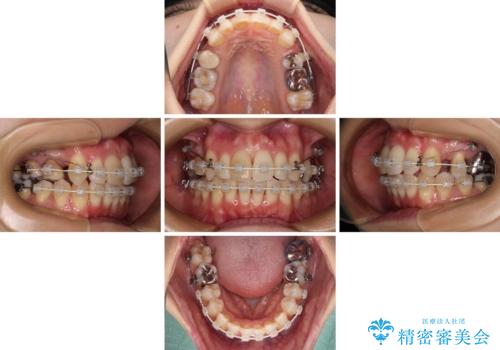

- 矯正装置

- 審美装置

- 3年7ヶ月

- 10-30回